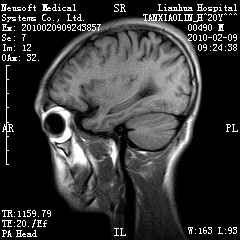

20岁男性患者,平时偶有头痛而无其他不适,现因持续头痛服药后无缓解而来院就诊。

松果体囊肿?

松果体区占位继发轻度脑积水?该患者有ct资料,我已发上。

考虑松果体囊肿。